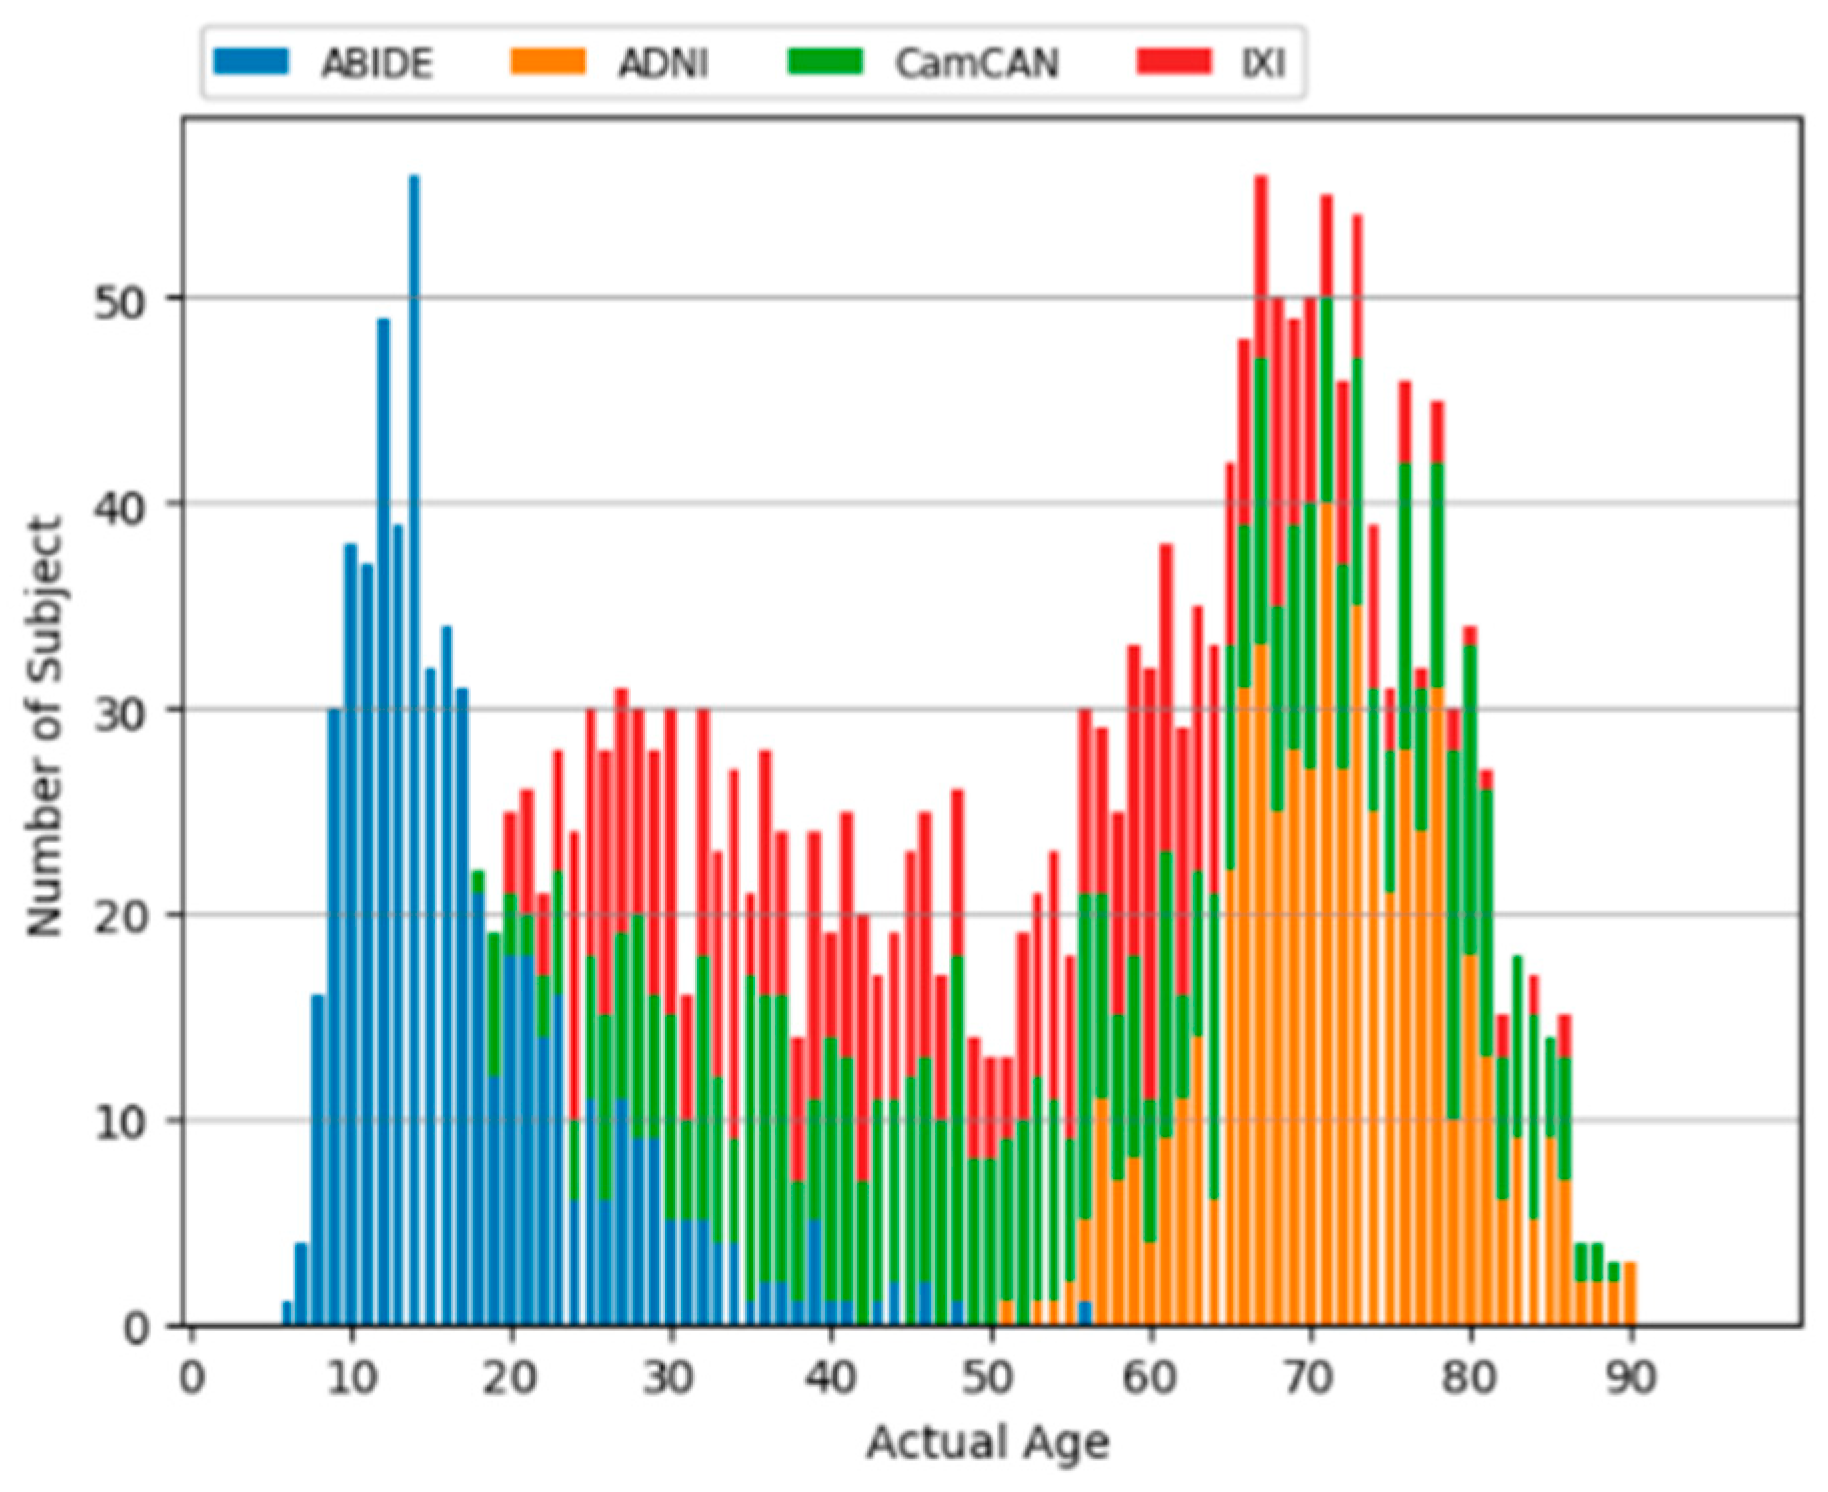

3.1. Data Sets